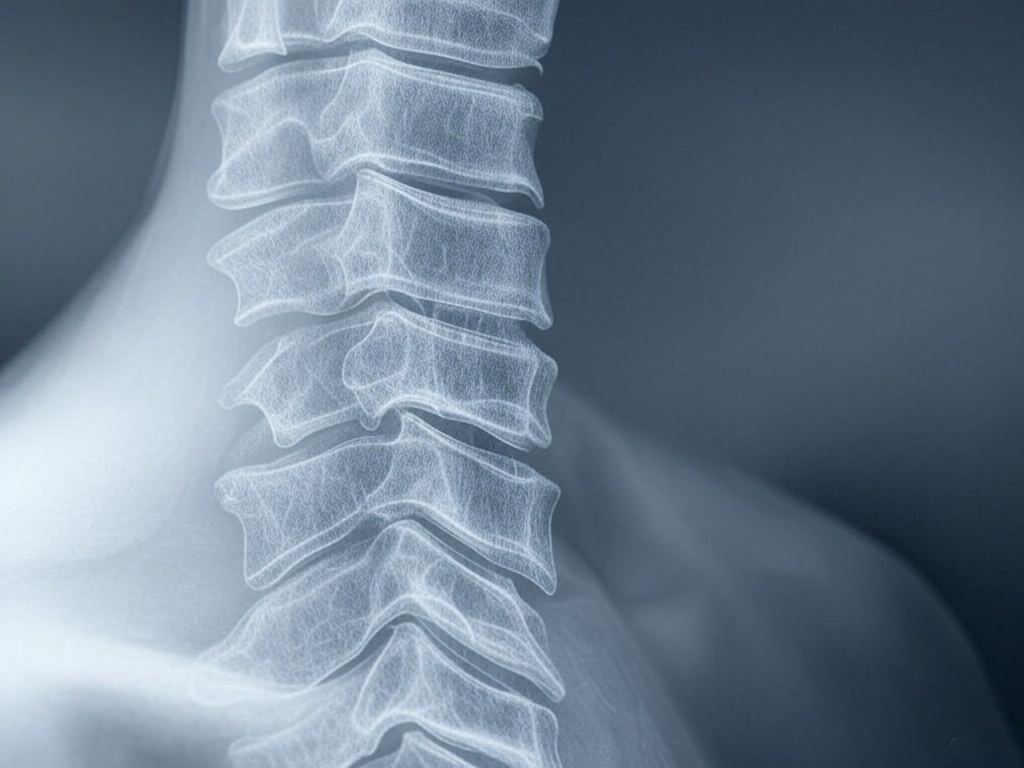

Радикулит — это поражение нервных корешков спинного мозга, входящих в межпозвонковые отверстия. В большинстве случаев причиной его развития являются дегенеративно-дистрофические процессы в позвоночнике, такие как остеохондроз, межпозвонковые грыжи, деформирующий спондилёз и другие патологии. В местах соединения позвонков происходит отложение солей, что приводит к потере эластичности межпозвонковых дисков и сдавливанию нервных корешков.

• Шейный радикулит — сопровождается односторонней болью в шее, плечах, затылке. Боль усиливается при движении головы, чаще всего возникает утром после сна или при физическом и психическом перенапряжении. Возможны головокружение, снижение остроты зрения и ослабление слуха.